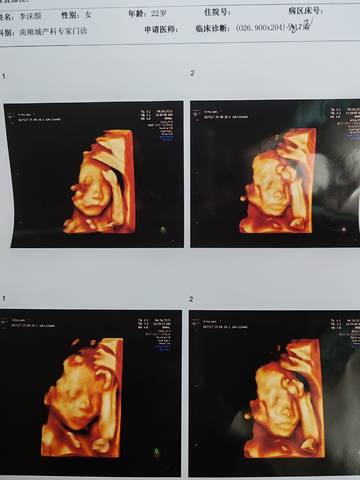

四维三次过,能看出女孩男孩吗,医生说有一样建议复查,现在太小了

那这胎儿检查图片还有单子看不出来,这主要检查胎儿脖颈透明度,数据值在正常的范围之内,已经顺利通过了,无论什么希望你能如愿。

从这个上面的话,一般是判断不出来的,如果医生建议复查的话,那么后续再去复查看一下的